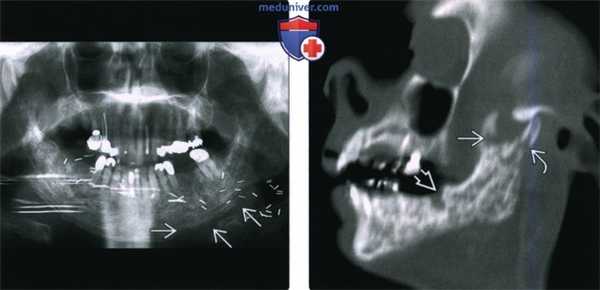

(Слева) При аксиальной КТ в коаном окне определяется патологическая мягкая ткань, заполняющая левый наружный слуховой канал (НСК) и ячейки сосцевидного отростка с явной деструкцией задней стенки ВСК и перегородок в сосцевидном отростке. Обратите внимание на смешанные склеротические и литические изменения костей - типичный вид височной кости при остеорадионекрозе.

(Справа) При аксиальной КТ в костном окне определяется радиационно-индуцированный некроз костного НСК и сливная деструкция ячеек сосцевидного отростка. Обратите внимание на «плавающий» костный секвестр. Все изменения указывают на тяжелый остеорадионекроз.